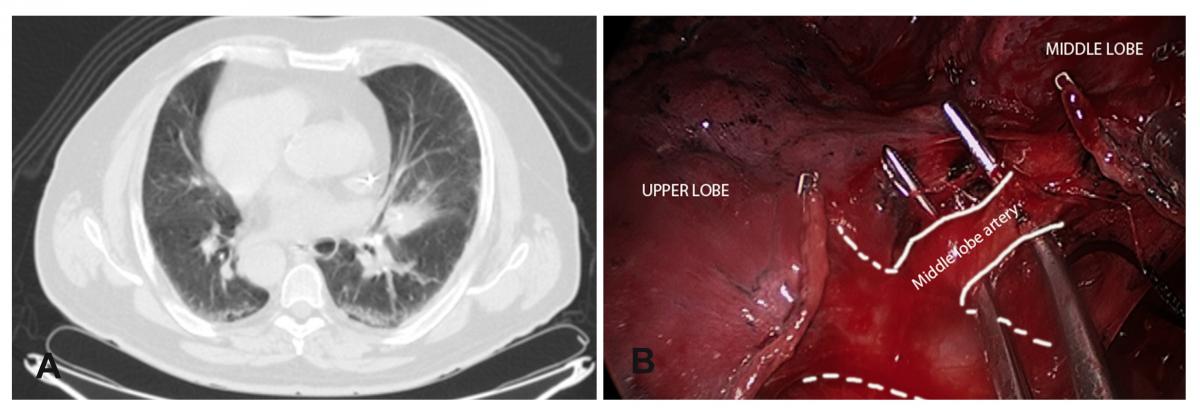

Surgical technique:The patient was placed in a right lateral decubitus position. An uniportal video-assisted thoracoscopic approach through a single 4 cm incision was made in the left 5th intercostal space with no rib spreading. The left lung composed of three lobes and vascular and bronchial anatomy was exactly as a normal right side lung. Azygos vein, superior vena cava, and paratracheal space were mirror images of normal condition (Fig. 1A,B).

A 3cm mass was located in the middle lobe (Fig. 2A), too large and deep to perform a wedge resection so a middle lobectomy (Fig. 2B) with complete lymphadenectomy was performed (paratracheal and subcarinal space). A single chest tube was placed in the posterior part of the incision.